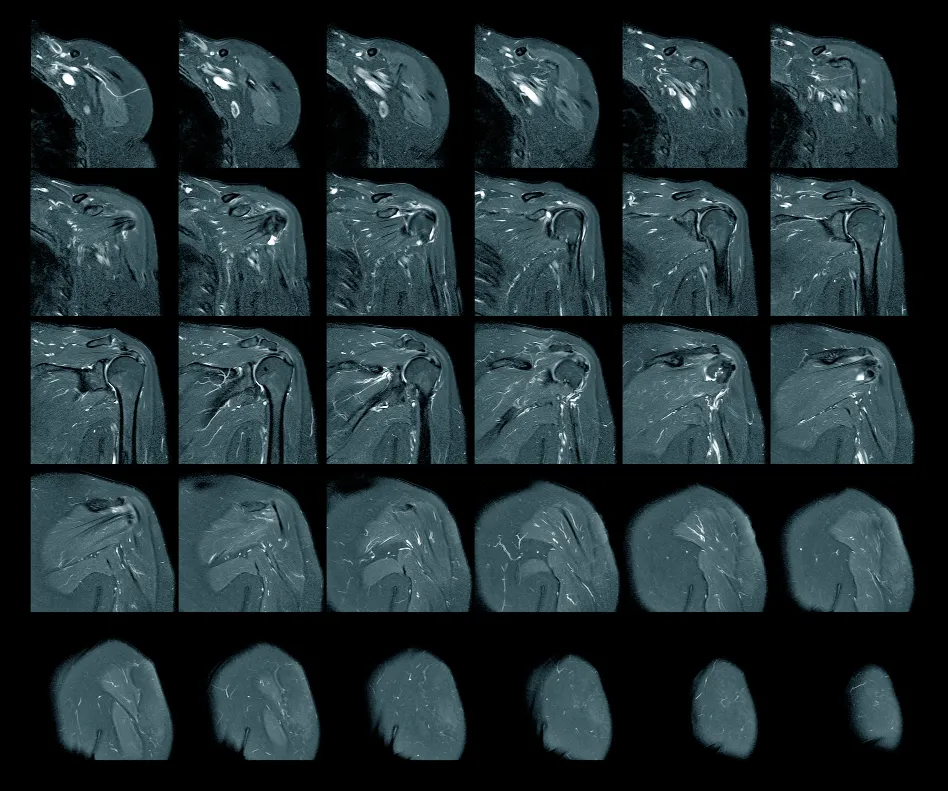

For the most complete diagnosis of shoulder pain, an x-ray and even an MRI can also be important. While x-rays are best for viewing joint deterioration and alignment of the shoulder, MRI is the best imaging for diagnosis of muscular, ligamentous damage, or torn rotator cuff. Sometimes MRI can complicate the diagnosis process, as previous injuries can sometimes show positive findings – even if they are not contributing to the current shoulder pain.